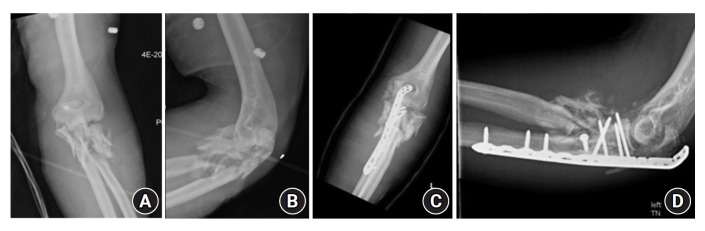

Results: Twenty-four patients were identified. All patients received prophylactic antibiotics upon admission and underwent urgent surgical debridement. Open reduction and internal fixation (ORIF) was performed with initial debridement in 22 of 24 patients. Seven patients sustained distal humerus fractures, 10 patients sustained isolated proximal ulna or proximal radius fractures, and seven had combined fracture patterns. Eleven patients presented with nerve palsy, and two had transected nerves. Two patients had vascular injury requiring repair. One patient required a temporary elbow-spanning external fixator and underwent staged debridement followed by ORIF. One patient with a grade IIIC fracture developed a deep infection that precluded ORIF. One patient required revision ORIF due to fracture displacement.

Abstract Image